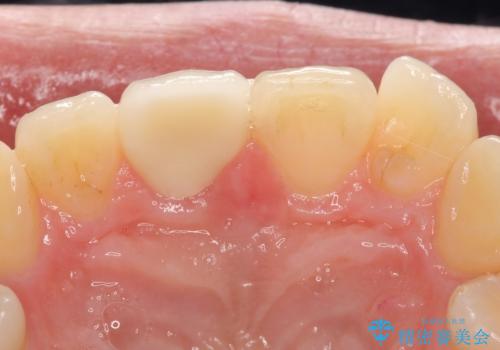

オールセラミッククラウン 痛みの引かない歯の治療

マイクロスコープ下でラバーダムを使用しながら根管治療を行い、痛みが治まった後にオールセラミッククラウンによる補綴を行いました。

今回用いたオールセラミッククラウンはジルコニアフレームという白い素材の上にセラミックを盛っているため、審美性が非常に高いのが特徴です。

また、ジルコニアは人工ダイヤモンドの材料にも使われているほど高い強度を持っており、そのためオールセラミッククラウンは審美性だけでなく、奥歯やブリッジの補綴も可能とするクラウンです。